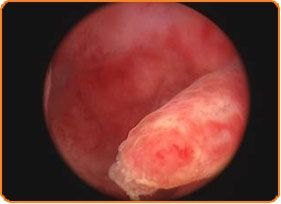

О”О№ОұОіОҪПүПғП„О№ОәО® ОҘПғП„ОөПҒОҝПғОәПҢПҖО·ПғО·

О— ОҙО№ОұОіОҪПүПғП„О№ОәО® П…ПғП„ОөПҒОҝПғОәПҢПҖО·ПғО· ОөОәП„ОөО»ОөОҜП„ОұО№ П„О¬ПҮО№ПғП„Оұ ОәОұО№ ОұОҪПҺОҙП…ОҪОұ, ПҢПҖПүПӮ ОјО№Оұ ОөПҖОҜПғОәОөПҲО· ОіО№Оұ test О ОұПҖОұОҪО№ОәОҝО»О¬ОҝП…, ОөОҪПҺ ОұПҖОҝП„П…ПҖПҺОҪОөП„ОұО№ ПғОө video ПғОұОҪ О№ОұП„ПҒО№ОәПҢ ОұПҒПҮОөОҜОҝ. TОҝ ОөПғПүП„ОөПҒО№ОәПҢ П„О·ПӮ ОјО®П„ПҒОұПӮ, Оҝ ПҮПҺПҒОҝПӮ ОөОјПҶПҚП„ОөП…ПғО·ПӮ П„ПүОҪ ОөОјОІПҒПҚПүОҪ ОәОұО№ ПҶО№О»ОҝОҫОөОҪОҜОұПӮ П„ОҝП… ОәП…О®ОјОұП„ОҝПӮ ОұПҖОҝП„ОөО»ОөОҜ ПғО®ОјОөПҒОұ ПҖПҒОҝПғОІО¬ПғО№ОјО· ПҖОөПҒО№ОҝПҮО®.

Оҹ ОӯО»ОөОіПҮПҢПӮ П„О·ПӮ ОјОө П„Оҝ П…ПғП„ОөПҒОҝПғОәПҢПҖО№Оҝ ОҙО·О»ОұОҙО® ОјОө О¬ОјОөПғО· ПҢПҒОұПғО· ОјОұПӮ ОҙОҜОҪОөО№ ПғО·ОјОұОҪП„О№ОәОӯПӮ ПҖО»О·ПҒОҝПҶОҝПҒОҜОөПӮ ОіО№Оұ ПҖОұПҒО¬ОіОҝОҪП„ОөПӮ ОјОөО№ПүОјОӯОҪО·ПӮ ОіОҝОҪО№ОјПҢП„О·П„ОұПӮ, ПҢПҖПүПӮ:

О•ПҖОөОјОІОұП„О№ОәО® ОҘПғП„ОөПҒОҝПғОәПҢПҖО·ПғО·

О— ОөПҖОөОјОІОұП„О№ОәО® П…ПғП„ОөПҒОҝПғОәПҢПҖО·ПғО· ОұПҖОҝП„ОөО»ОөОҜ О¬О»О»О· ОјОҜОұ ПғПҚОіПҮПҒОҝОҪО· ОҙП…ОҪОұП„ПҢП„О·П„Оұ ПҖОҝП… ОөОәП„ОөО»ОөОҜП„ОұО№ ПғП„Оҝ ОәОӯОҪП„ПҒОҝ ОјОұПӮ. О‘ПҖОұО№П„ОөОҜ ОұОҪОұО№ПғОёО·ПғОҜОұ ОәОұО№ ОіО№вҖҷ ОұП…П„ПҢ ОөОҪОҙОөОҜОәОҪП…П„ОұО№ ОҪОұ ОіОҜОҪОөП„ОұО№ ОұПҖОҝОәО»ОөО№ПғП„О№ОәО¬ ОәОұО№ ОјПҢОҪОҝ ПғОө ОұПғПҶОұО»О® ПҮПҺПҒОҝ ПҢПҖПүПӮ О· ОәО»О№ОҪО№ОәО® П„ОҝП… ОәОӯОҪП„ПҒОҝП… ОөОҫПүПғПүОјОұП„О№ОәО®ПӮ ОіОҝОҪО№ОјОҝПҖОҝОҜО·ПғО·ПӮ В«ОңОҷОӨО©ОЈО—В».

ОҡОұП„О¬ П„О· ОҙО№ОұОҙО№ОәОұПғОҜОұ ОұП…П„О®, ОјПҖОҝПҒОҝПҚОјОө ОҪОұ ПҖПҒОҝПҮПүПҒО®ПғОҝП…ОјОө ОјОө ОұПғПҶОұО»О® ОәОұО№ ПҮПүПҒОҜПӮ ОөПҖО№ПҖО»ОҝОәОӯПӮ П„ПҒПҢПҖОҝ, ОәОұО№ ОәП…ПҒОҜПүПӮ ПғОө ПҖОҝО»ПҚ ПғПҚОҪП„ОҝОјОҝ ПҮПҒПҢОҪОҝ, ПғОө ОөПҖОөОјОІО¬ПғОөО№ПӮ ПҖОҝП… ОұОҪП„О№ОјОөП„ПүПҖОҜО¶ОҝП…ОҪ ПҖОұПҒО¬ОіОҝОҪП„ОөПӮ ПҖОұПҒОұОјПҢПҒПҶПүПғО·ПӮ П„О·ПӮ ОјО·П„ПҒО№ОәО®ПӮ ОәОҝО№О»ПҢП„О·П„ОұПӮ, ОұПҖОҝП„ПҒОҝПҖО®ПӮ ОөОіОәП…ОјОҝПғПҚОҪО·ПӮ ОәОұО№ ПҖПҒПҢОәО»О·ПғО·ПӮ ОұПҖОҝОІОҝО»ПҺОҪ, ПҢПҖПүПӮ: